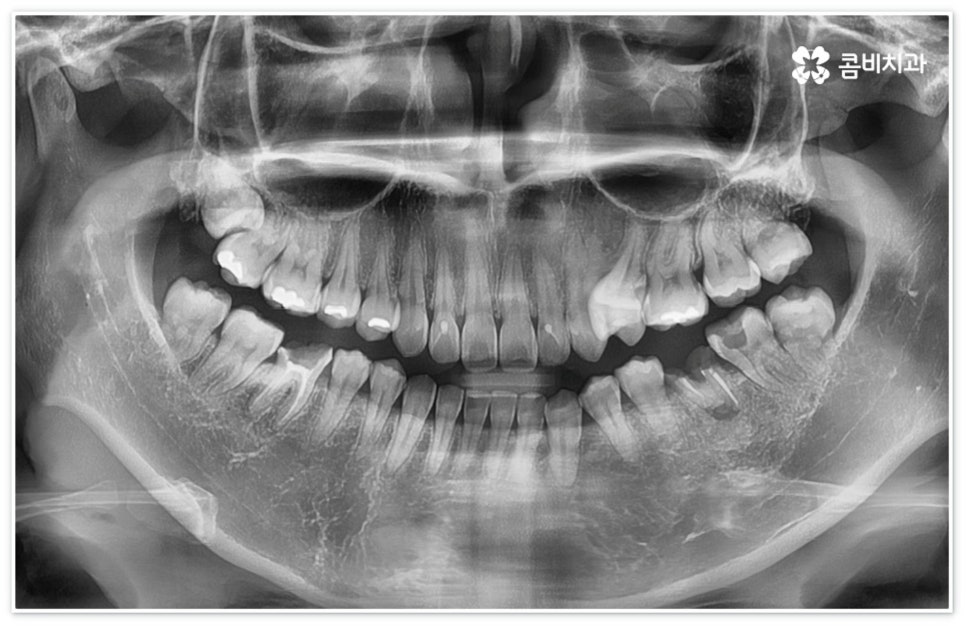

당분을 먹이로 삼아 증식하면서 산성 물질을 만들어내는 박테리아 때문에 치아에 손상을 입게 되는 구강 질환이 충치인데, 겉부분인 법랑질에 막 발생하기 시작했을 때는 해당 부위에 신경이 존재하지 않기 때문에 환자분들의 입장에서 별다른 통증도 느껴지지 않고 겉으로 봤을 때 색이나 모양 등 차이점이 크게 두드러지지 않지만 시간이 지날수록 욱신거리는 통증도 심해지고 색깔도 불투명한 흰색을 지나 점차 갈색, 까만색으로 벌레가 먹은 듯이 보이게 되므로 자각 증상이 있거나 눈에 띄는 변화가 있을 때는 지체하지 말고 치과로 내원하셔서 검진과 치료를 받아보시길 권유드리고 있습니다.

만약 법랑질 또는 상아질 일부에만 충치가 생긴 초기에 이를 발견하고 바로 대처하면 손상이 적기 때문에 우식 부위를 깨끗하게 제거하고 레진 등으로 직접 치료하거나 인레이, 온레이 같은 방식을 통해 간접적으로 보철물을 끼워넣을 때도 좀 더 빠르고 간편한 수복이 가능할 수 있어요. 그러나 바빠서 시간을 낼 수 없거나 또는 약간의 두려움 내지 무심함으로 치과 내원을 미룬 경우 우식 부위가 점차 넓어져 해줘야 할 치료도 더욱 고난도로 복잡해지게 되며 치수 조직까지 되돌릴 수 없는 손상을 입었다면 신경치료가 불가피 할 거예요.

신경치료는 일견 간단해 보일 수 있으나 사람의 신경이 매우 얇고 또한 환자분들마다 신경관의 개수와 모양이 다 다르기 때문에 오염된 부위를 끝까지 깨끗하게 제거하기 위해서는 매우 섬세하고 뛰어난 기술력을 요하므로 다양한 임상 경험을 통해 풍부한 노하우를 가지고 있는 의료진과 함께 하실 필요가 있습니다.

이때 환자분들마다 상황이 다를 수 있는데 예를 들어 교정 치료 중 충치 치료 (신경 치료) 및 발치와 임플란트 식립과 같은 고난도의 치료들을 함께 진행해야 하는 복잡한 케이스의 경우에는 더욱 시술자의 숙련도가 중요하다고 할 수 있어요. 의료진의 자격증, 경력 사항, 분과별 협진 여부 등을 잘 알아 보시고 필요한 치료들을 모두 통합적으로 진행할 수 있는지, 또한 환자분들의 상황을 꼼꼼하게 살필 수 있는 3D CT 와 같은 정밀 검진 기계를 갖추고 있는지 등을 체크해 보신 후에 처음부터 끝까지 책임 진료하는 의료진과 철저한 케어 시스템을 갖추고 있는 치과를 선택하셔서 제 때 필요한 치료를 받으시길 권유드리고 있습니다.